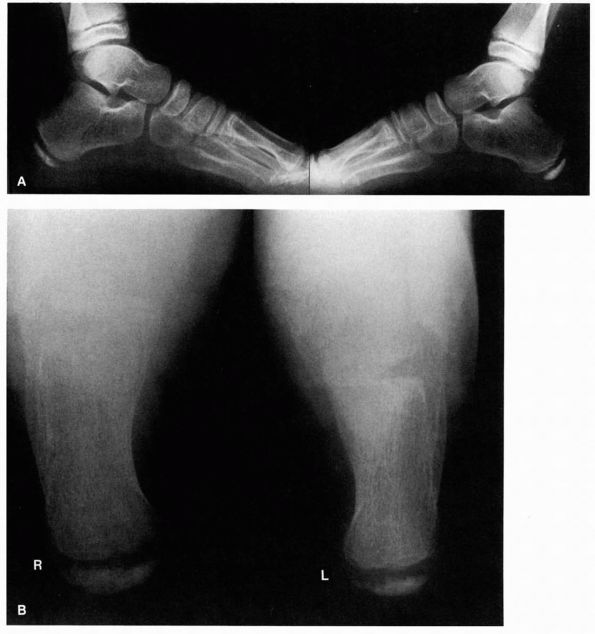

![]() |

FIGURE 20-21. Tarsal coalition. Note the position of the involved left foot with the forefoot in abduction (A) and heel in valgus (B). Also note the loss of the longitudinal arch.

generally reveals decreased hindfoot or midfoot motion, or both. Most

commonly, the heel is in valgus and the forefoot in abduction (Figure 20-21).